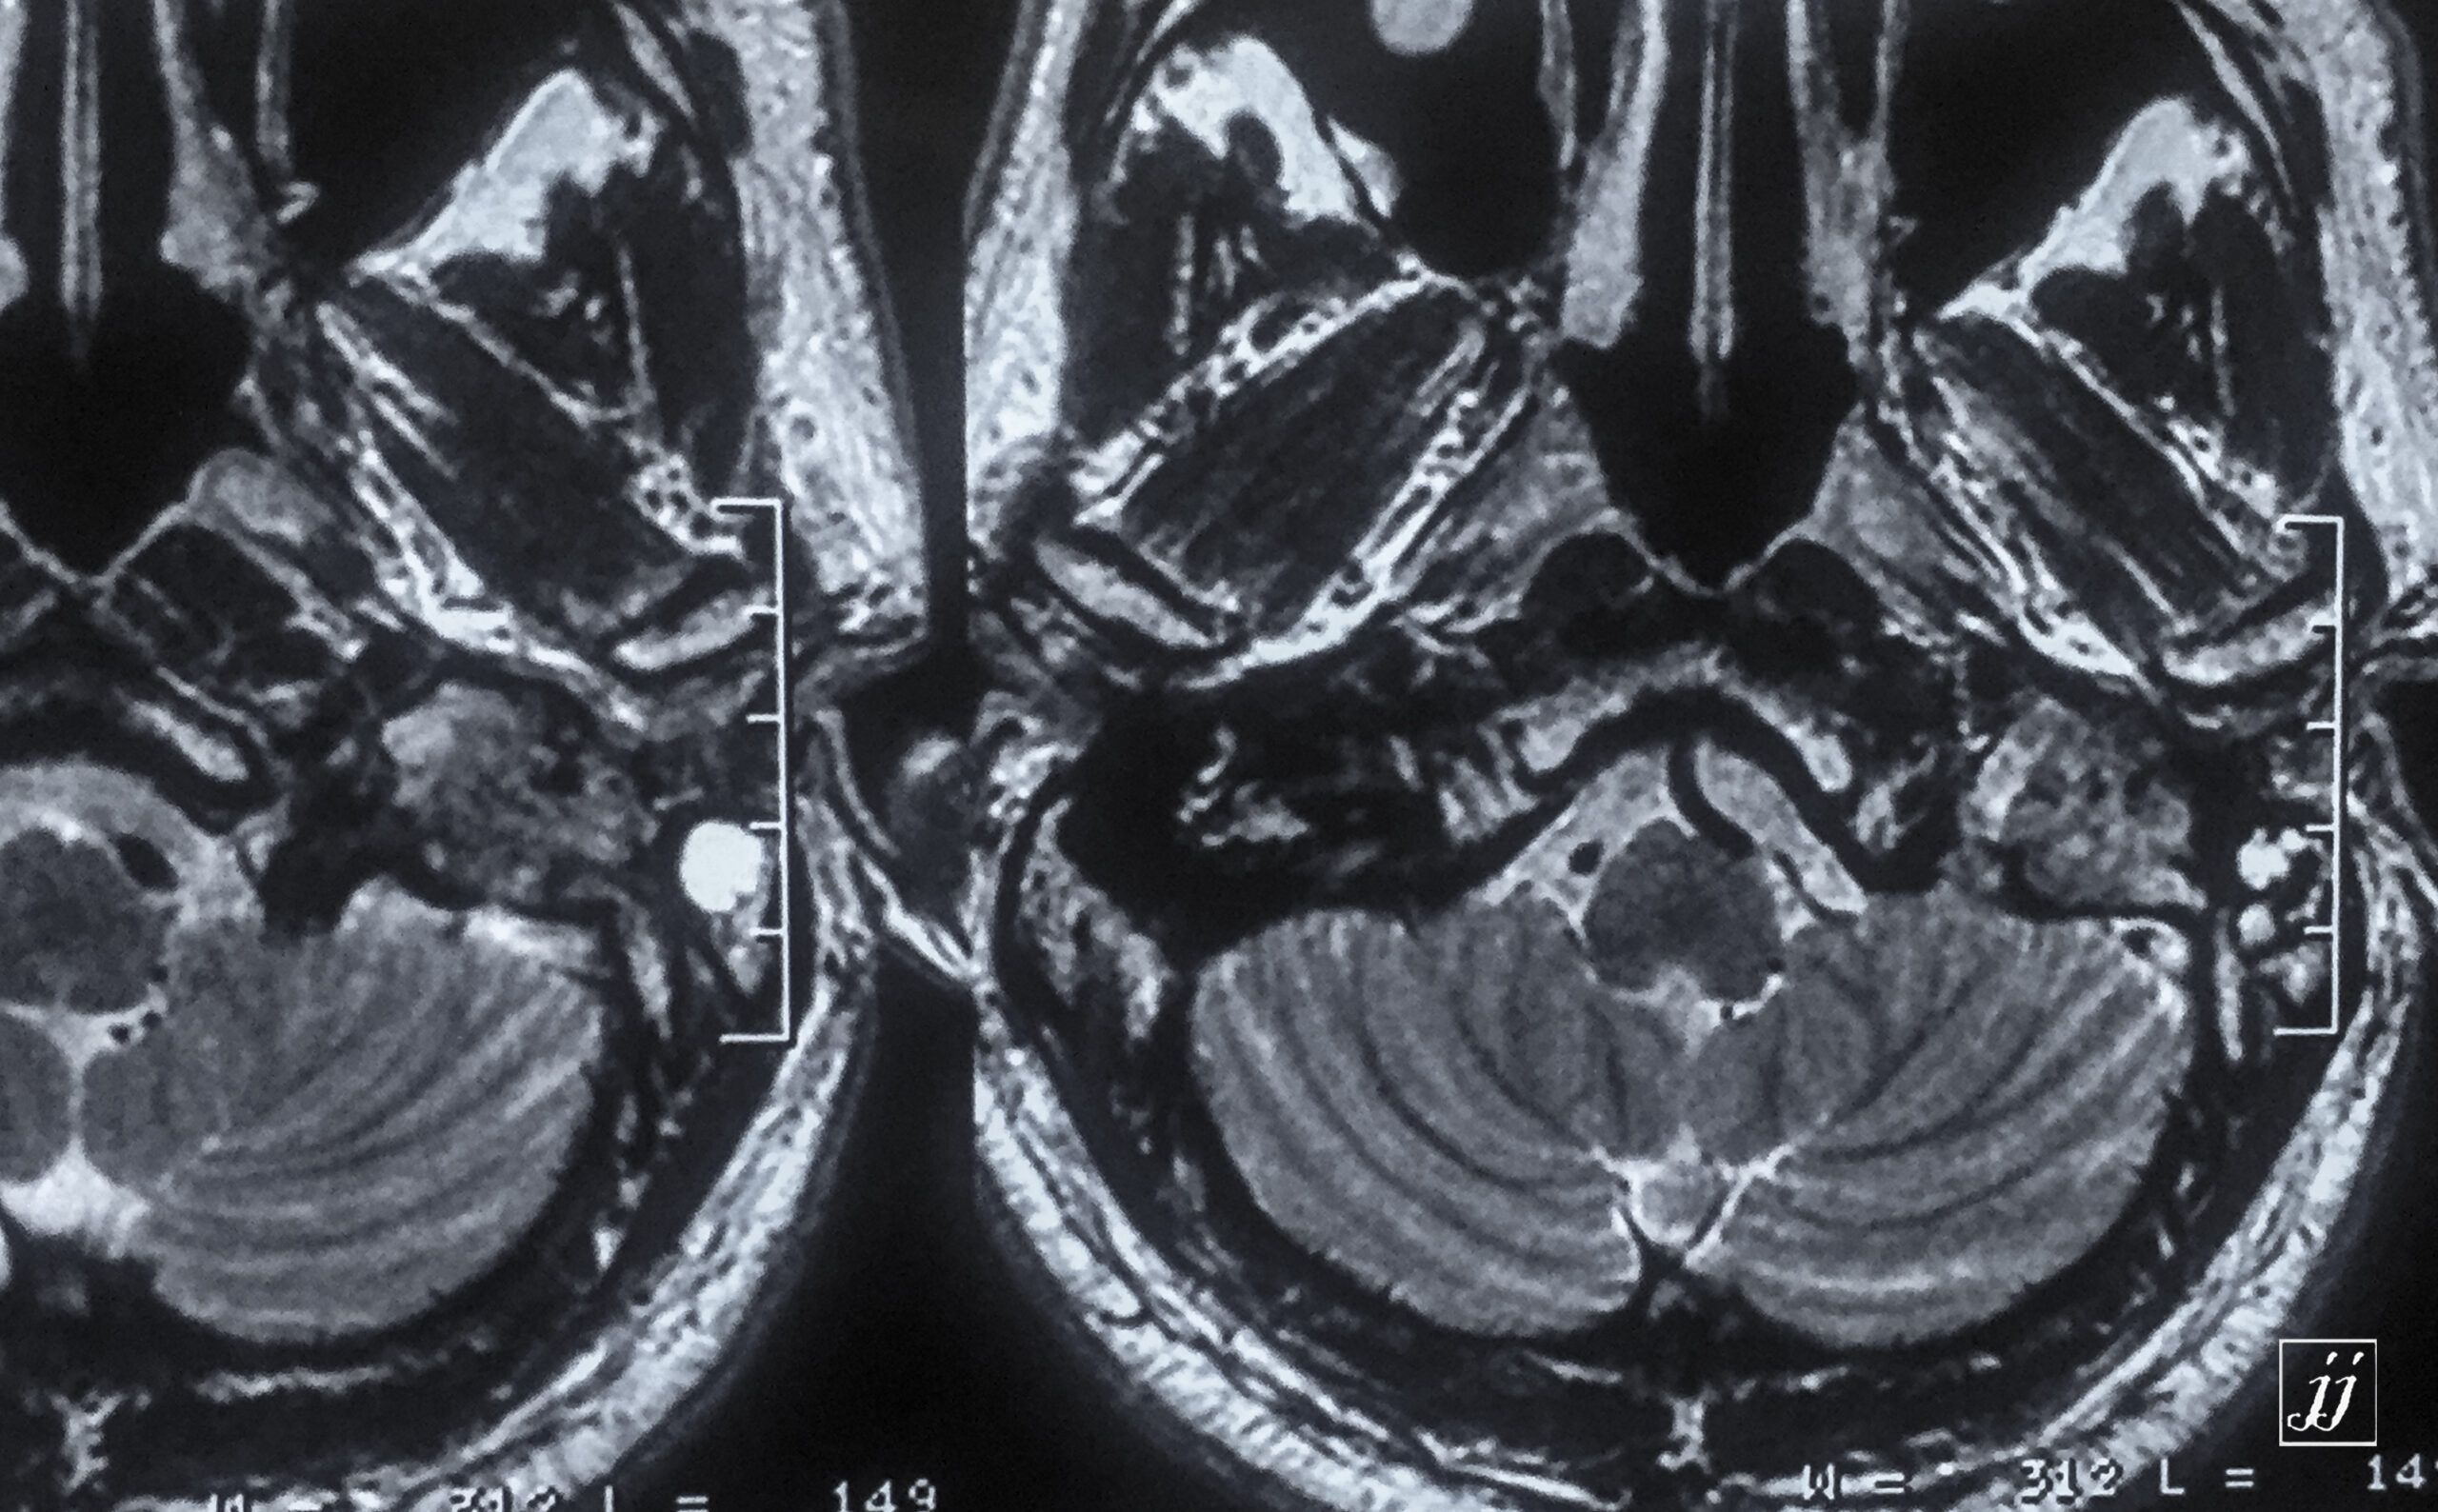

Brain- left side COM (4)